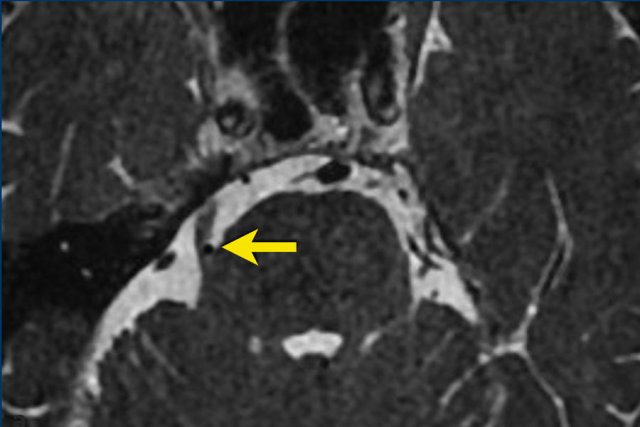

These images are of a 49-year old male with sensory problems in the left side of his face and pressure behind his left eye.

The axial T2W shows a lesion in Meckel’s cave and the cisternal segment of the trigeminal nerve. The component in Meckel’s cave is solid and shows homogeneous enhancement on post-contrast T1W imaging (arrow).

The component in the cerebellopontine cistern is almost completely cystic and shows only rim enhancement.

The lesion is a trigeminal schwannoma.

The growth of this lesion along the nerve, leading to a constriction at the entrance of Meckel’s cave, causes the classic ‘dumbbell shape’.